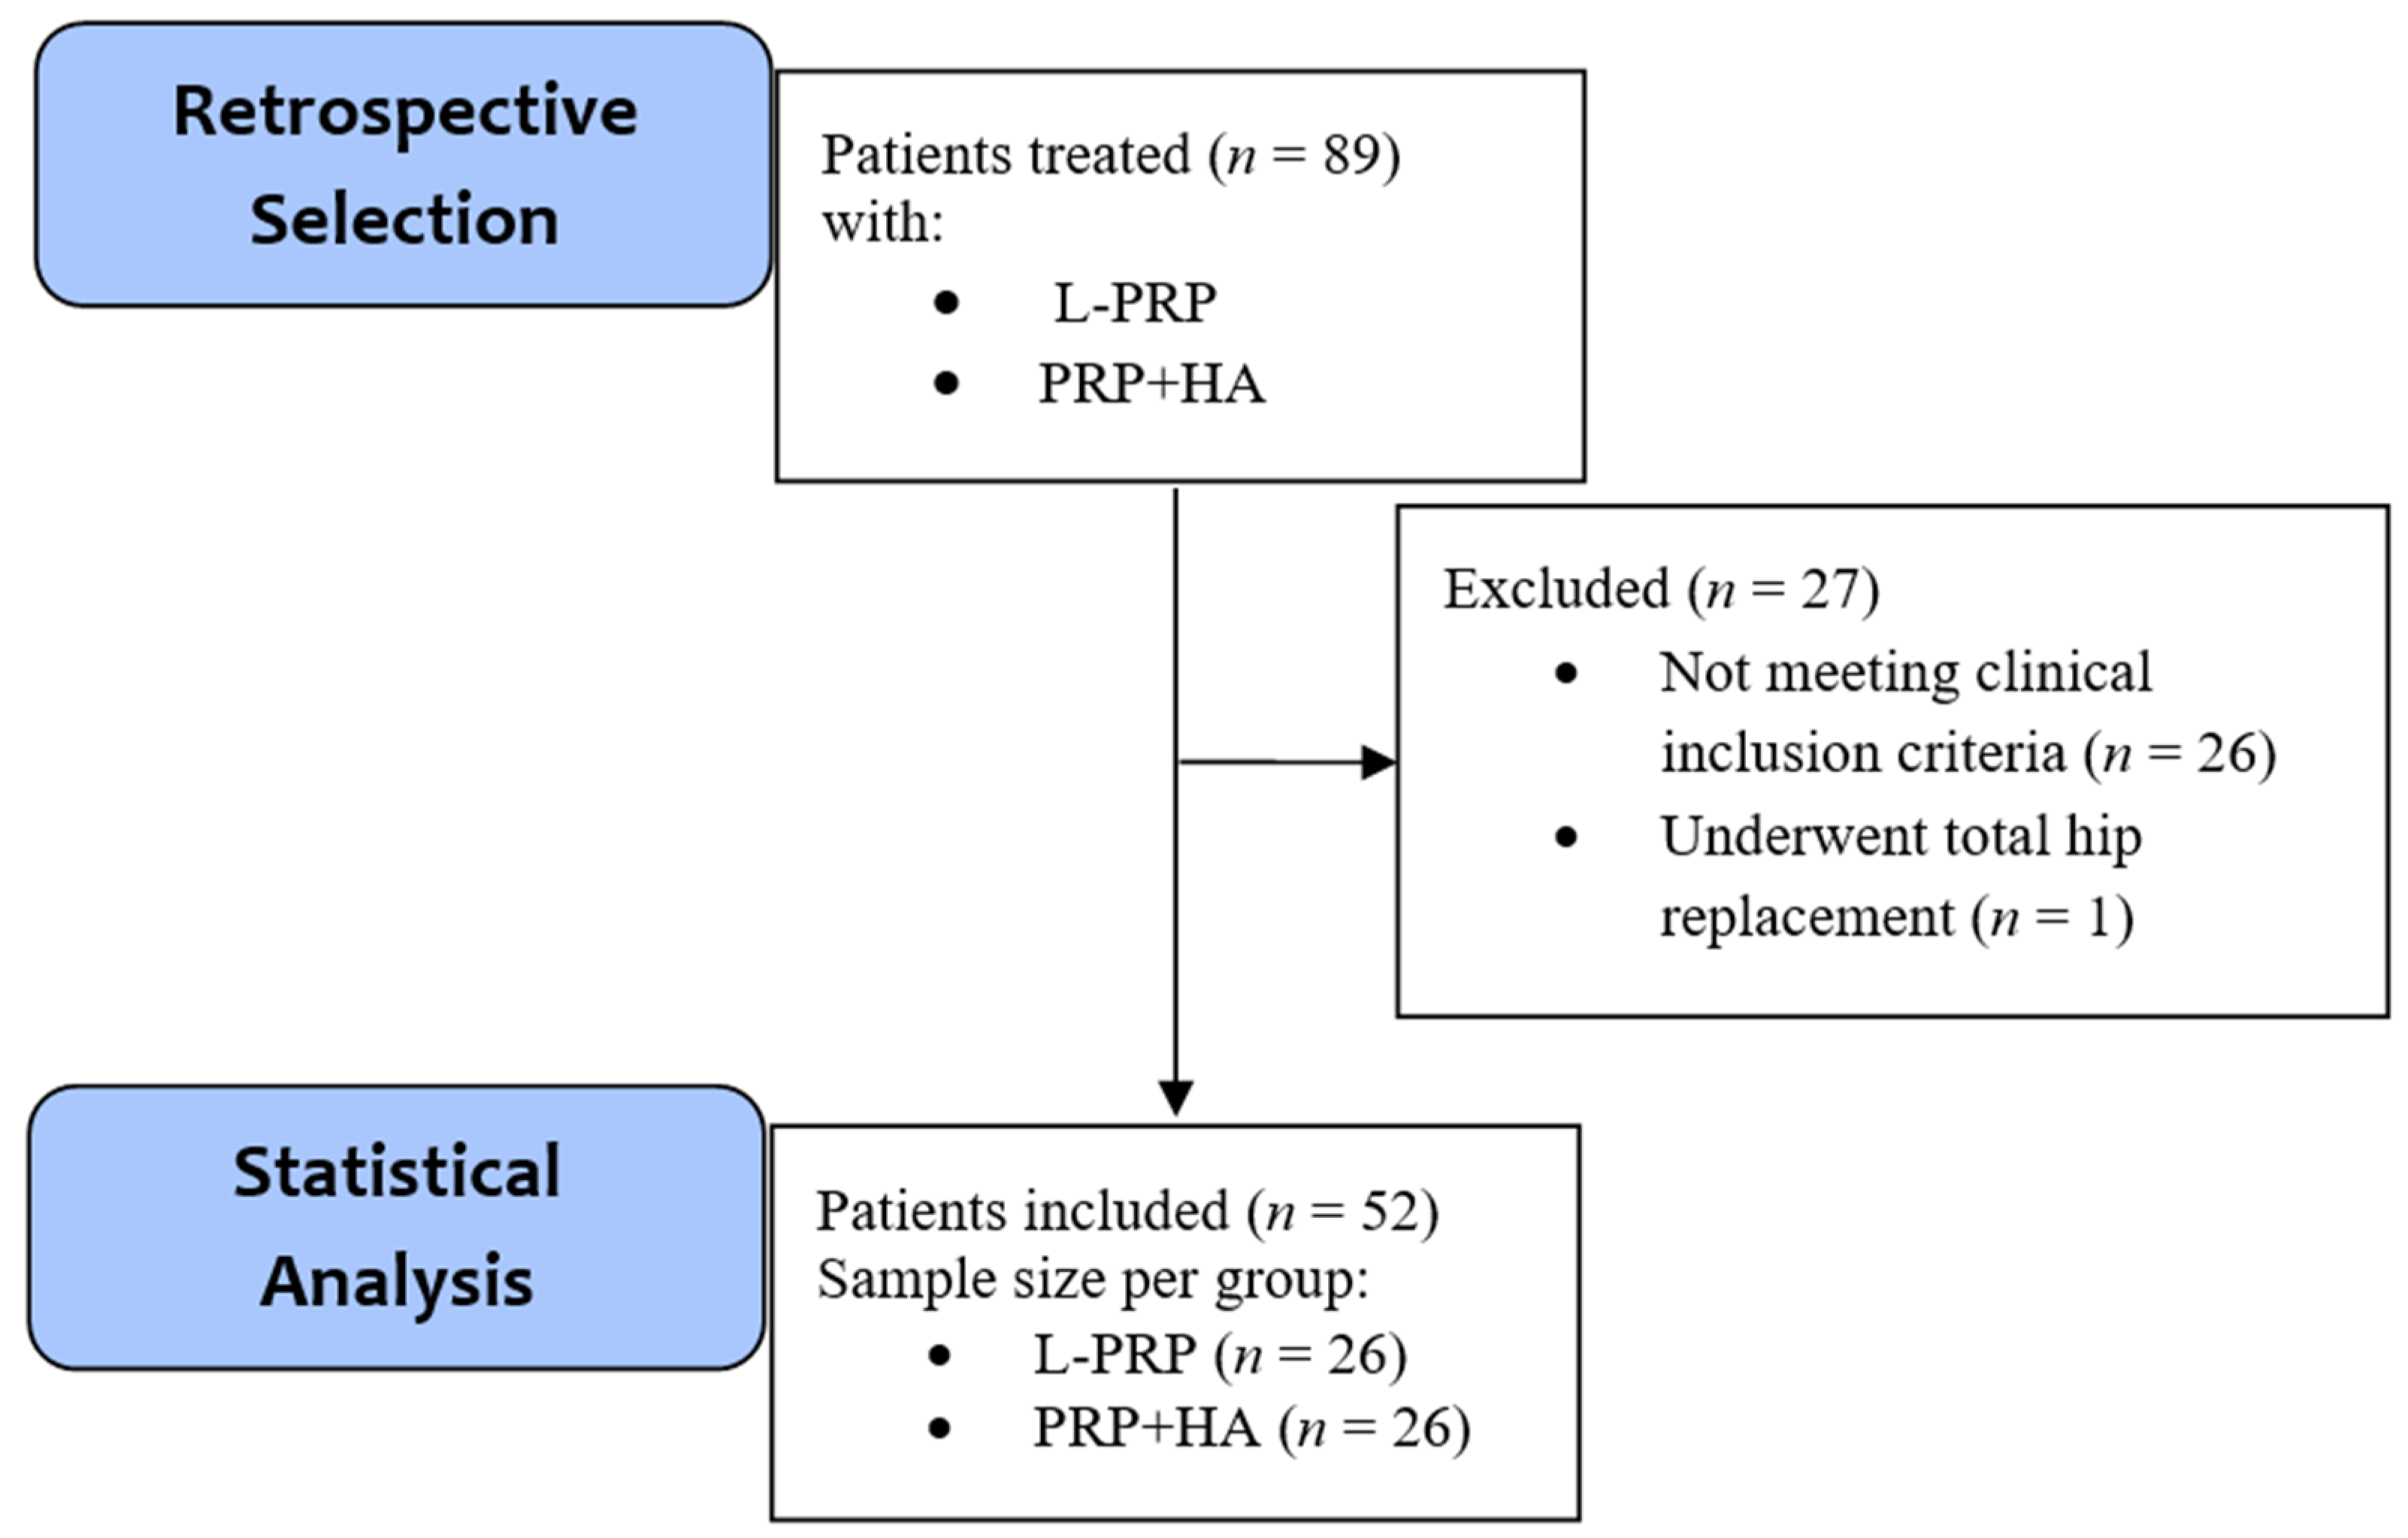

4.1. Study Design

4.1.1. Patient Selection